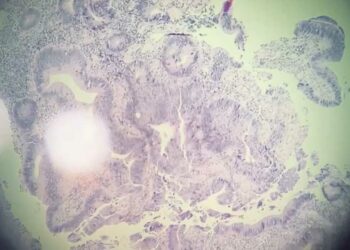

Офтальмоонколог Республиканской клинической офтальмологической больницы, доцент кафедры офтальмологии КГМУ Раушания Гайнутдинова сообщила о симптомах, указывающих на рак глаз, передает "Татар-информ". ...